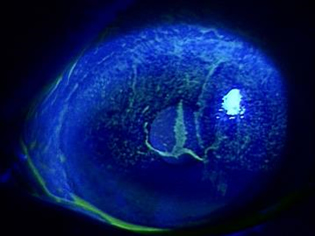

下記写真は角膜をフルオレセインで染色し、ブルーフィルターを通して撮影することで、角膜上皮の傷を分かりやすくしたものです。左の写真1は健常者の角膜で正常な状態で、傷がないので何も染まってません。対して、右の写真2はS-1内服患者さんの角膜です。

角膜中央から上方にかけて、広範囲に角膜上皮が障害されていることが確認出来ます。